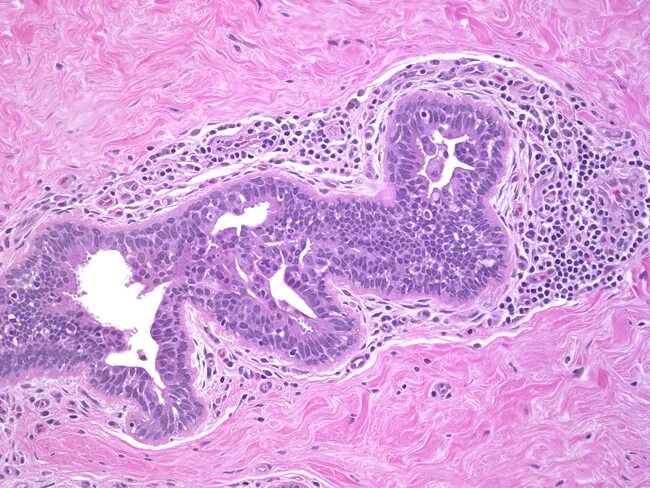

Мастит по студенцову